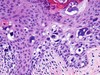

Newborn with clustered vesicles in an arcuate and polycyclic array

What type of EB is this?

EB simplex, Dowling-Meara (EBS-DM) subtype

- Split seen within basal keratinocytes

- Clumping of tonofilaments within keratinocytes’ cytoplasm